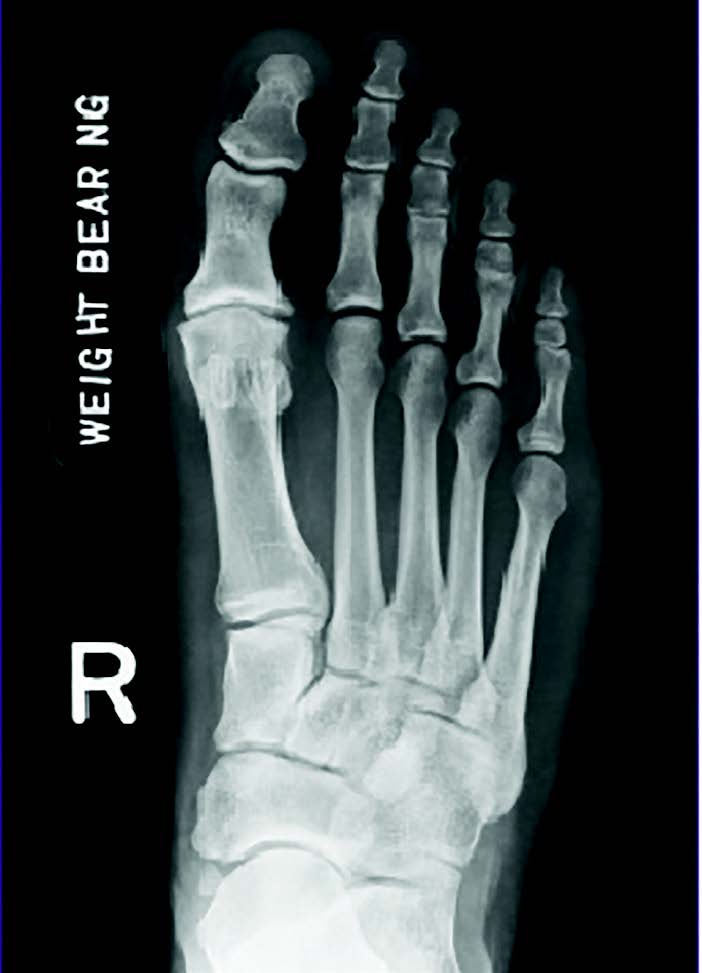

It is important to order the proper diagnostic testing in conjunction to one’s examination. We always begin with standard radiographs (full weight-bearing anterior-posterior, medial oblique and lateral). Adding in a sesamoid axial view is not a bad idea to look at the position and quality of the sesamoid complex. What I look for in radiographs is the position of the metatarsal, the degree of joint space narrowing and the degree of spur formation. What is the quality of the great toe joint? However, don’t forget to also check the overall position and alignment of the foot.

What I have realized is that with standard radiographs alone, I miss a significant amount of diagnostic information that led me to some suboptimal results. I feel this may have proven avoidable if I had additional information. I thought some cases were simple cheilectomy procedures that I later found that osteochondral lesions primarily caused the pain. Others seemed to have smooth and fluid motion in the central aspect of the joint, which ended up having far worse arthritic changes than I expected when I opened the joint. The question is; how can we know the quality of the joint and the health of the cartilage and bone prior to surgery?

CT is, in my observation, overall a great exam to show anatomic position of the metatarsal, the level of dorsal spurring, and the actual jamming angle of the joint. A weight-bearing CT is preferrable, as I feel this gives true positional information. What I prefer to use more often is an MRI of the great toe joint. I find it more useful to help me diagnose osteochondral damage, subchondral damage to the metatarsal head, and to check the overall quality of the cartilage prior to surgery. This helps me plan my procedure and avoid an intraoperative surprise.